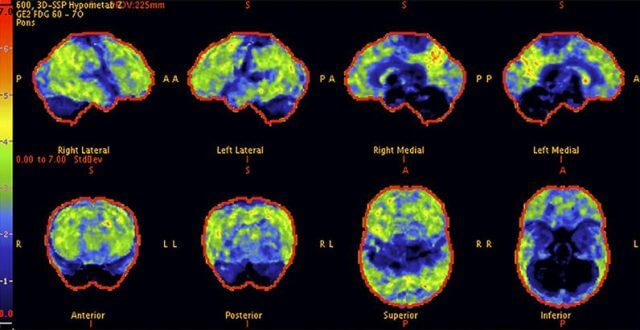

Above: A 68-year-old woman with a 10-year history of cognitive issues. Previous PET scans showed significant metabolic decline, indicating Alzheimer’s.